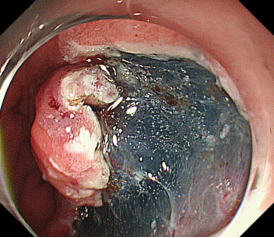

早期胃癌及内镜手术

消化道早癌的病例展示(经内镜手术或活检证实):

胃角的腺癌

胃窦的腺癌 行ESD治疗

术中见较粗穿支血管,裸化后凝除,最终高效、安全的切除病灶。